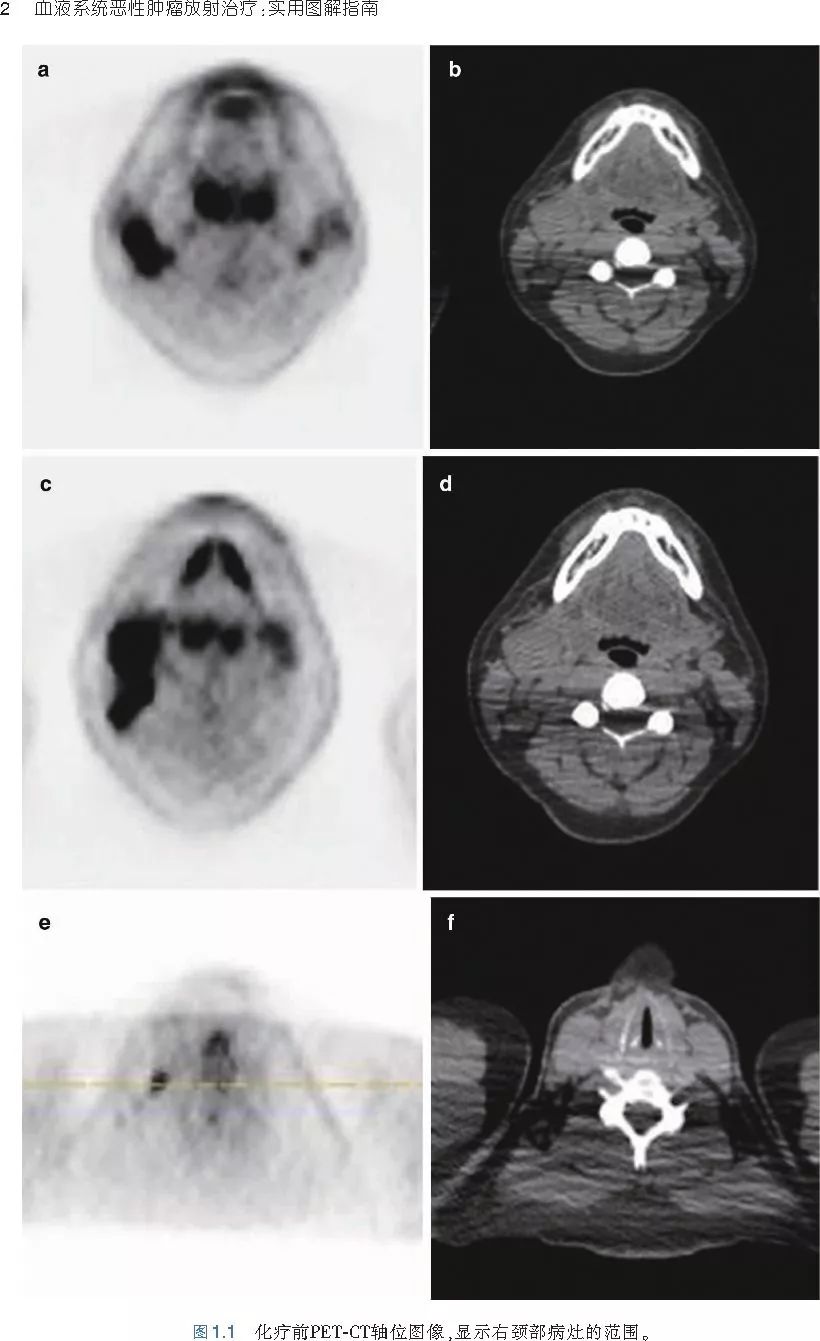

本书旨在帮助临床医生对常见血液系统恶性肿瘤疑难病例进行管理,包括霍奇金淋巴瘤、非霍奇金淋巴瘤和白血病患者,并通过多个病例进行阐述。案例讨论遵循标准格式,包括临床描述,其次是与诊断相关的病理描述和分期,然后详细讨论治疗选择。最后,确定治疗方案,并提供所使用的规划放疗技术/方式的图像。对放射肿瘤医生进行临床决策非常有帮助,对于血液病临床医生也有很好的指导作用。

近年来,放射治疗技术得到了迅速发展,调强放疗、图像引导放疗及其他新技术方法等,对恶性肿瘤治疗产生了巨大影响。现代放疗技术使精确定位、靶区勾画及给量成为可能,实现了肿瘤局控率和生活质量的双赢,对血液系统恶性肿瘤的临床治疗也产生了一定的影响。此书内容上不仅反映了血液系统恶性肿瘤综合治疗的进步,更是对其中放射治疗的新变化进行了系统、详细的阐述,这对当前血液系统恶性肿瘤放射治疗临床实践具有非常好的指导作用和参考价值。